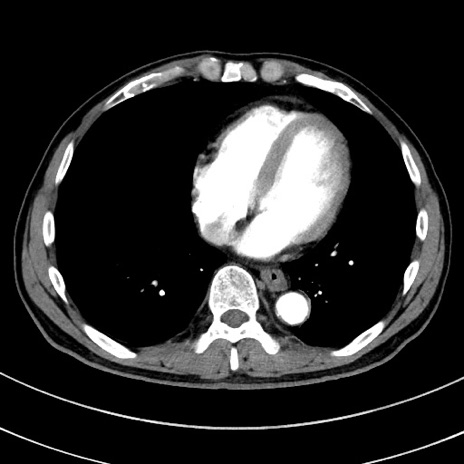

症例8(横断像)

【症例】 60歳代男性

【主訴】 黒色吐物

【現病歴】 4日前から嘔気自覚、2日前の朝食後にも嘔気あり、自分で手で嘔吐反射起こし嘔吐したところ血が混ざっていたため受診。

【既往歴】 5年前汎発性腹膜炎を伴う急性虫垂炎で手術、高血圧、前立腺肥大症、高脂血症

【身体所見】 腹部正中に手術癩痕あり 腹部平坦・軟圧痛なし膨満感あり

【データ】WBC 8400、CRP 4.54